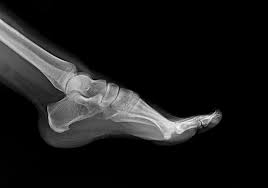

Trn v peti: vzroki, simptomi in učinkovite metode zdravljenja

Trn v peti (plantarni fascitis) povzroča bolečine pri hoji in športu. Preberi, zakaj nastane, kako ga zdravimo ter kako ti lahko pomaga 5-tedenski protokol masaže in vaj.